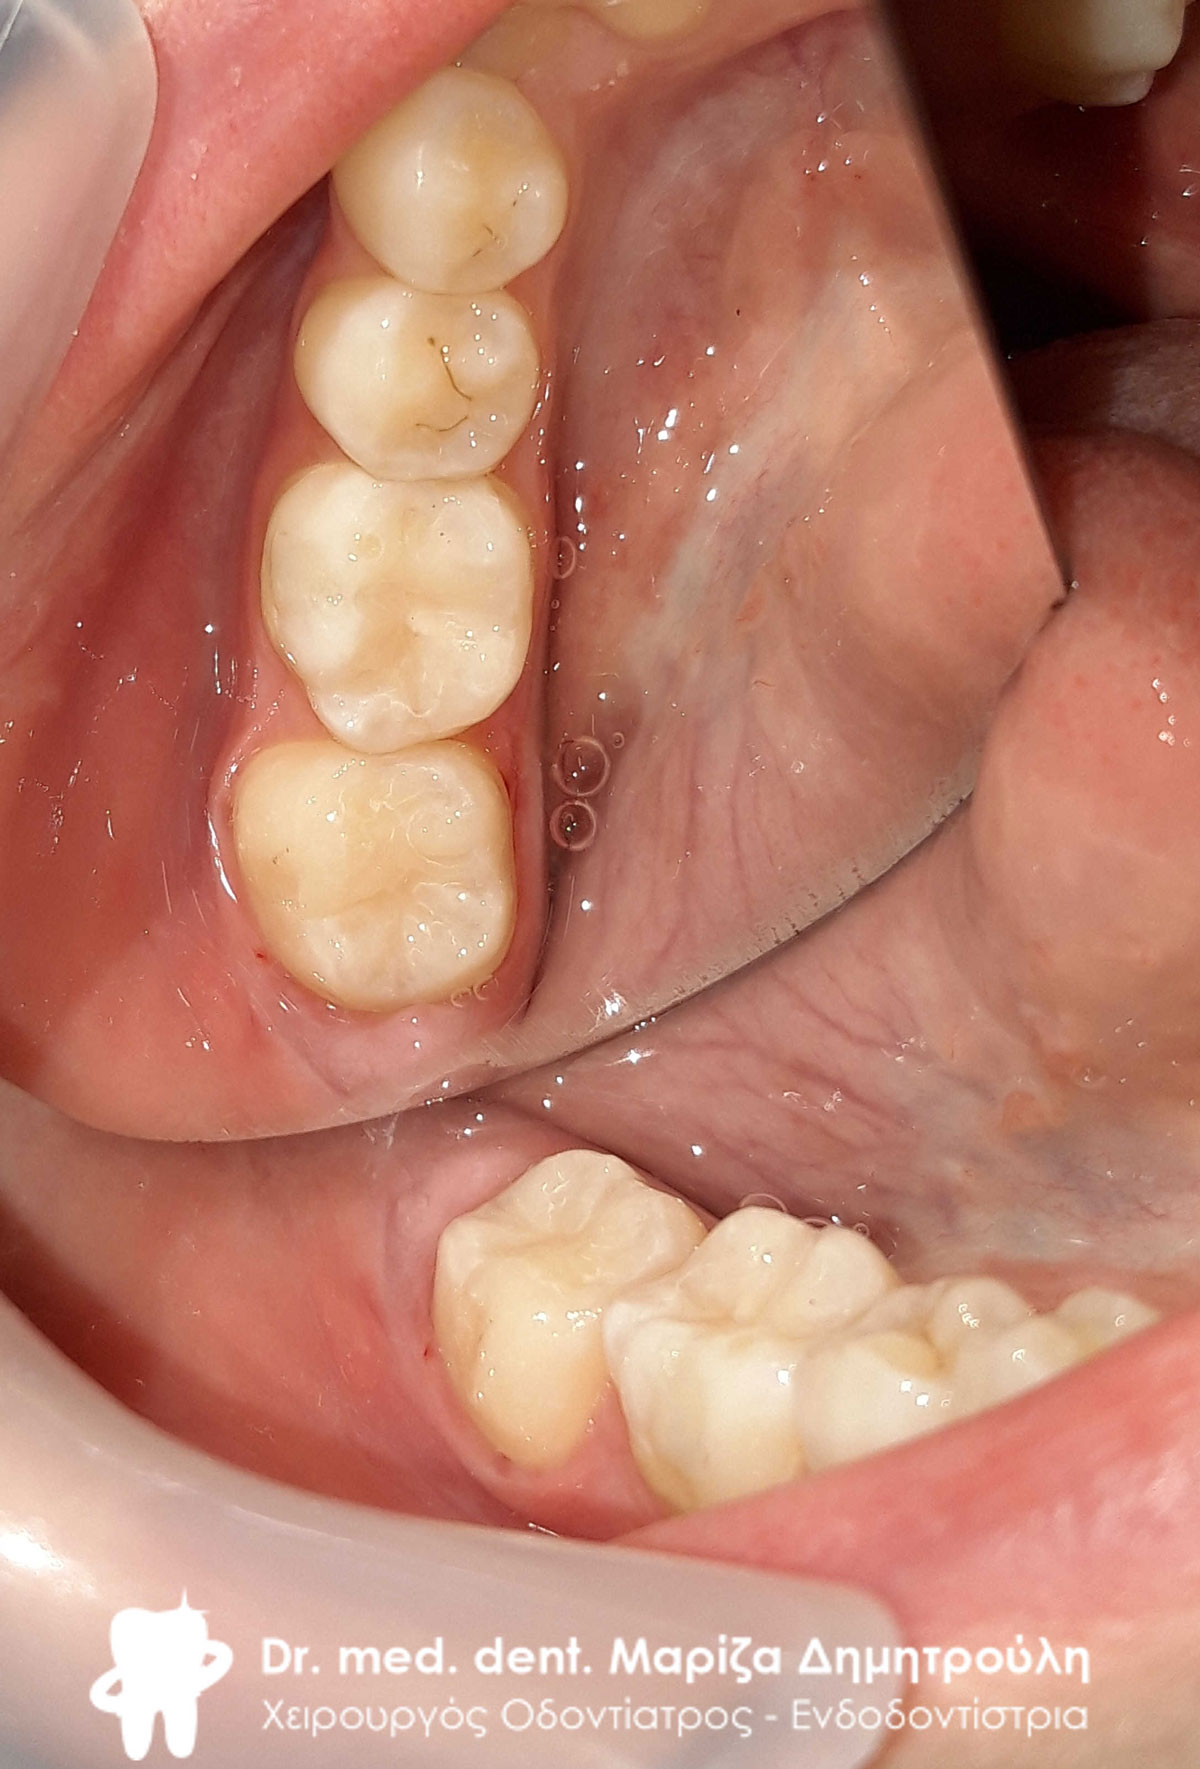

Αρχική κλινική εικόνα της αριστερής πλευράς της άνω γνάθου

Λευκά σφραγίσματα στους άνω προγομφίους

Πλήρης αποκατάσταση της άνω αριστερής πλευράς με λευκά σφραγίσματα